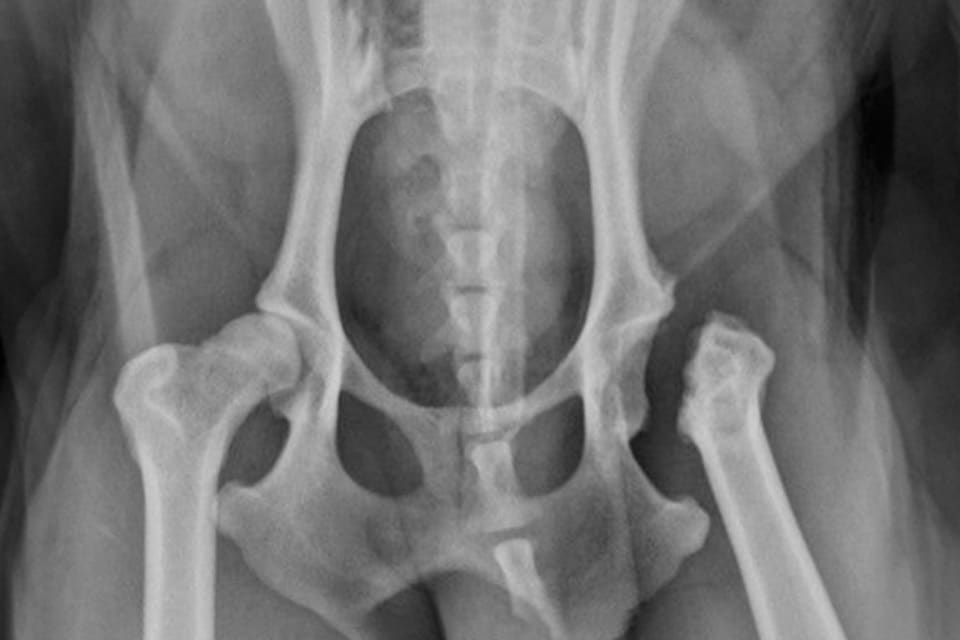

A Femoral Head Ostectomy is a surgical procedure that removes the head and neck of the femur to relieve pain caused by hip conditions such as hip dysplasia, osteoarthritis, or fractures. This procedure creates a “false joint,” eliminating bone-on-bone contact and allowing scar tissue and muscle support to restore mobility. FHO surgery is most effective for small- to medium-sized dogs. Schedule a consultation to find out if this procedure is right for your pet.

Femoral Head Ostectomy